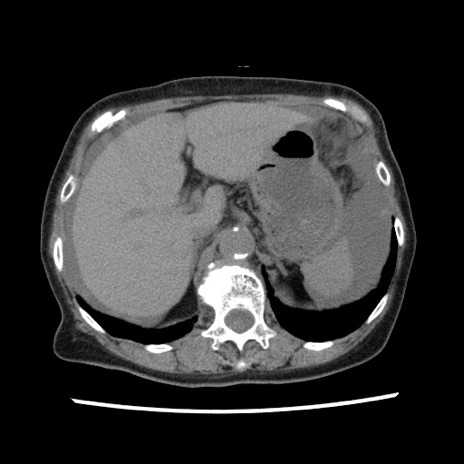

冠状断像

【症例】80歳代女性

【主訴】腹痛

【現病歴】8時間前から腹痛あり来院。

【既往歴】糖尿病、脂質異常症、子宮体癌にて子宮全摘術

【身体所見】意識清明・会話良好だが腹痛で苦悶様、全腹部にわたって反跳痛と圧痛あり

【データ】WBC 13600、CRP 0.14、LDH 224、CK 90